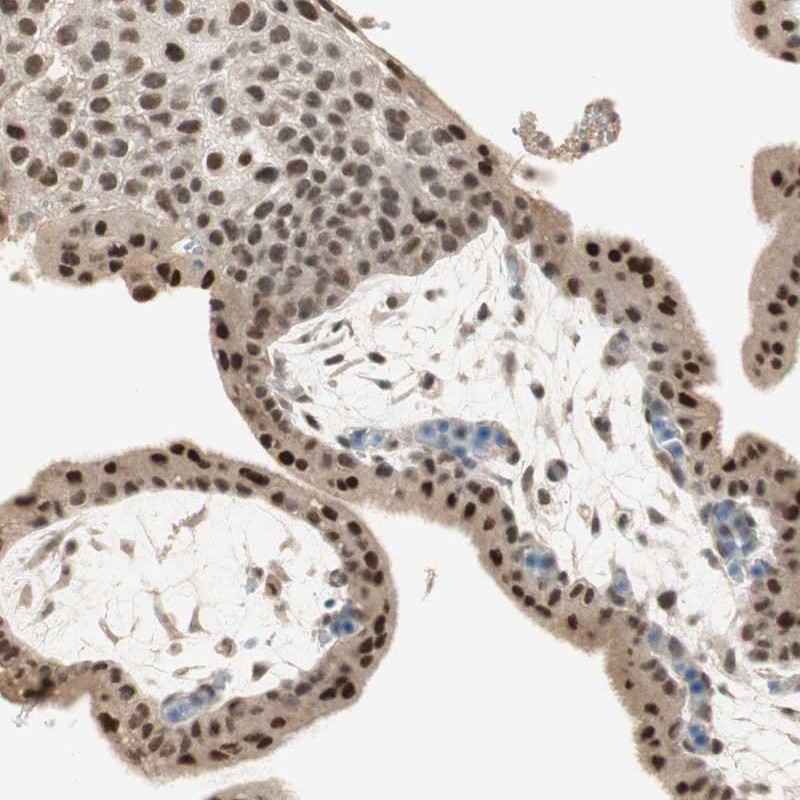

Immunohistochemical staining of human placenta shows strong nuclear positivity in trophoblastic cells and decidual cells.